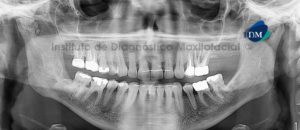

Paciente femenino, 55 años de edad acude al Instituto de Diagnóstico Maxilofacial (IDM) para su evaluación previo a tratamiento integral y colocación de implantes. A